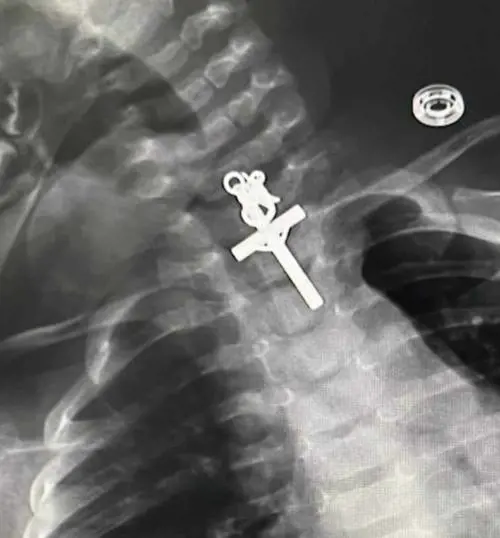

In Perù, una madre non riusciva a spiegarsi il pianto ininterrotto le difficoltà respiratorie evidenziate dalla figlia di dieci mesi. E la radiografia ha tolto ogni dubbio: la piccola aveva ingerito un crocifisso ed è stata operata d'urgenza